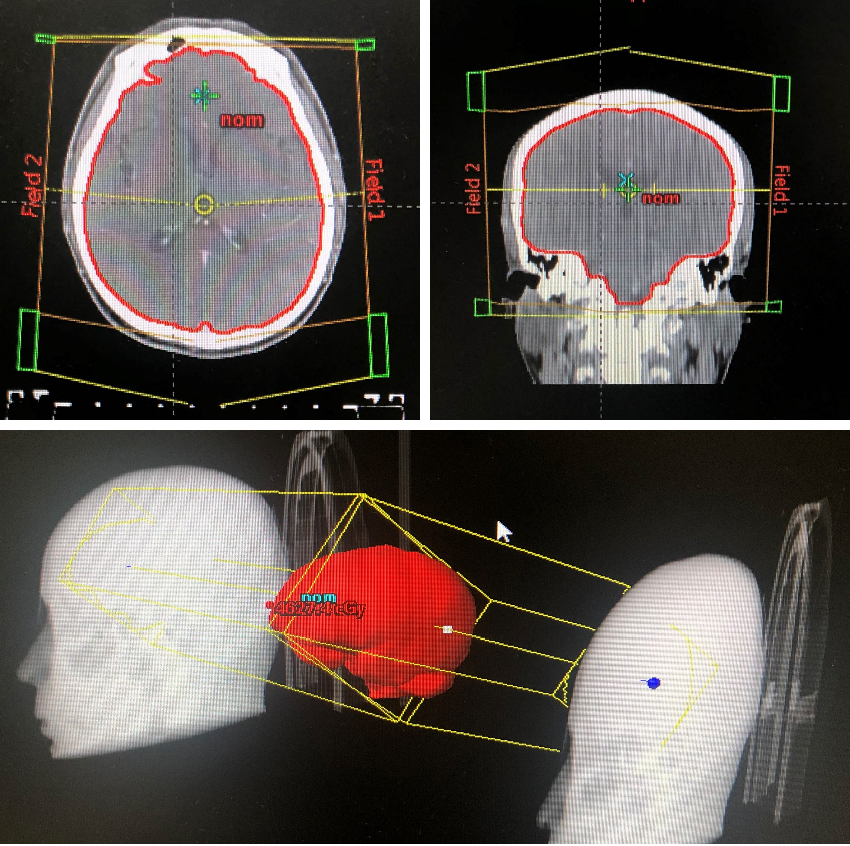

经患者充分知情同意并签署知情同意书后,考虑予以免疫联合化疗治疗。于2020年2月7日先行1周期EP方案化疗:“依托泊苷(VP-16)0.1g d1-4 + 卡铂500 mg d1,q3w,ivgtt”;于2020年2月6日至3月6日间行全脑放疗(46Gy/23f);于2020年2月28日起行免疫联合化疗:“替雷利珠单抗200 mg d1 + 依托泊苷 0.1g d1-4 + 卡铂500 mg d1,q3w,ivgtt”,至今已应用替雷利珠单抗治疗9周期。

图5:2020年2月6日至3月6日,行全脑放疗

本例患者为“左肺上叶小细胞癌(广泛期,cT3N1M1,IV期),伴左肺门淋巴结转移、多发脑转移”,考虑予以免疫联合化疗。为明确并监测患者可能出现的毒副反应,先予以患者1周期EP方案化疗,同时予以全脑放疗1个月。患者未出现明显不良反应,予以患者加用替雷利珠单抗免疫治疗2周期,疗效评价即达到PR,治疗6周期后疗效达到CR。随访至今PFS已超过7个月,疗效持续CR,安全性良好,患者可以耐受。